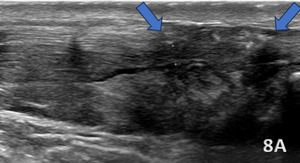

ACHILLES PERITENDONITIS

Figures 8A (LAX View) and 8B (SAX View):

Ultrasound findings of Achilles peritendonitis include a hypoechoic crescent (blue arrows) abutting the posterior surface of the distal Achilles tendon, with increased vascularity on Doppler imaging in the peritendinous region and Kager’s fat pad, without increased echogenicity. The Achilles tendon itself appears intact, with no signs of tendinosis. These findings differentiate peritendonitis, which affects the tissues surrounding the tendon, from tendonitis, which involves intrinsic changes within the tendon structure.